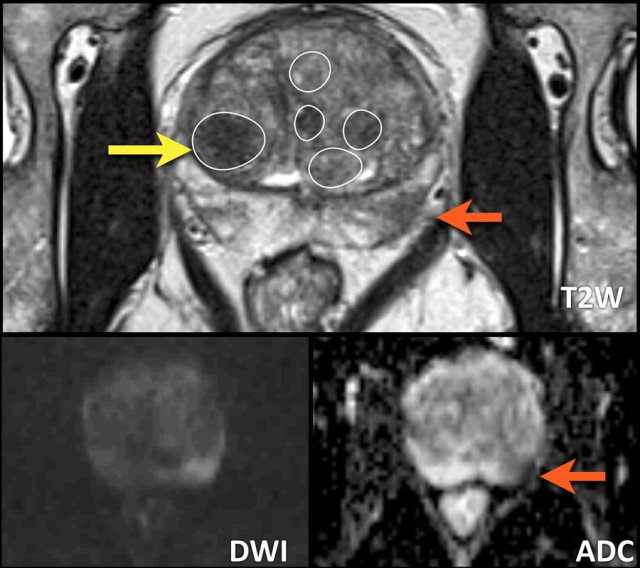

Examples of PI-RADS 1-5

Examples of PI-RADS scores 1-5 are given in the table.

In the peripheral zone, the PI-RADS assessment category of a lesion is determined primarily on DWI/ADC and correlated to T2W- and DCE-images.

In the peripheral zone an equivocal or indeterminate lesion (category 3) is assigned to PI-RADS category 4 if DCE is positive, i.e focal or earlier contrast enhancement.

The lesion remains assigned to PI-RADS category 3 if the DCE is negative, i.e. no early enhancement or diffuse enhancement and not corresponding to the focal T2W/DWI lesion or focal enhancement corresponding to BPH.

Peripheral zone

PI-RADS

For the peripheral zone the DWI/ADC is the primary determining sequence to assign the PI-RADS assessment category.

Peripheral zone - DWI/ADC category 1

- No abnormality visible on ADC and high b-value DWI.

Peripheral zone - DWI/ADC category 2

- Linear/wedge shaped configurations with hypointensities on ADC and/or linear/wedge shaped hyperintensities on high b-value DWI.

Peripheral zone - DWI/ADC category 3

- Focal (discrete and different from the background) hypointensity on ADC and/or focal hyperintensities on high 3 b-value DWI

- May be markedly hypointensity on ADC or markedly hyperintensity on high b-value DWI, but not both.

- A category 3 lesion remains a PI-RADS score 3 if there is no focal enhancement (negative), but becomes a PI-RADS score 4 if the enhancement is focal.

Peripheral zone - DWI/ADC category 4

- Focal markedly hypointensity on ADC and markedly hyperintensity on high b-value DWI

- <1.5cm in greatest dimension.

Peripheral zone - DWI/ADC category 5

- Same as as assessment score 4 but ≥1.5cm in greatest dimension or

- Definite extraprostatic extension (EPE) or invasive behavior.